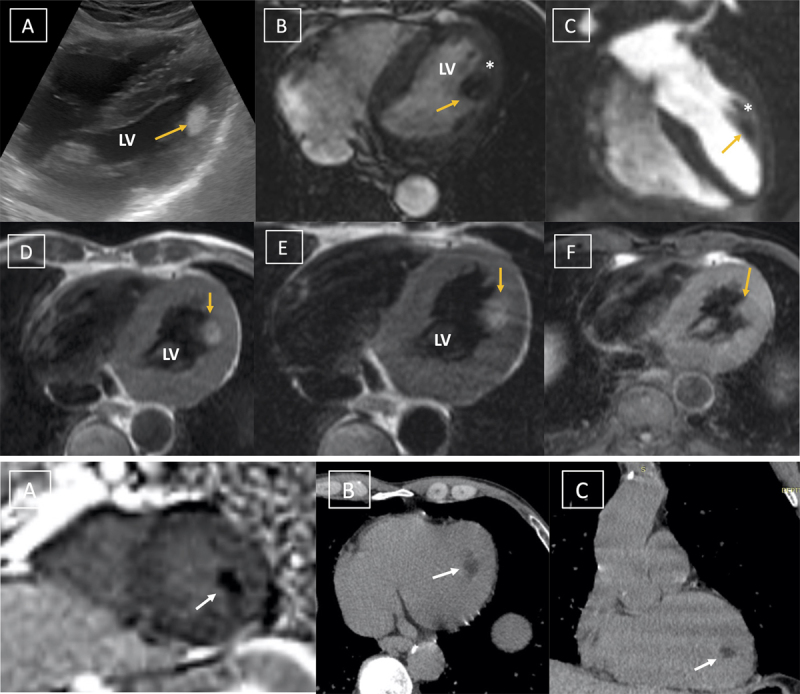

经胸超声心动图和心脏磁共振成像显示,一个轮廓清晰的球状肿块附着在前外侧乳头肌上。该肿块在 T1 和 T2 加权图像上呈高密度,在脂肪饱和和短头反转恢复(STIR)图像上信号抑制。乳头肌是脂肪瘤的一个非常罕见的部位,文献中鲜有报道。

Transthoracic echocardiography and cardiac magnetic resonance imaging revealed a well-defined globular mass attached to the anterolateral papillary muscle. The mass was hyperintense on T1 and T2 weighted images with suppression of signal on fat saturated and short tau inversion recovery (STIR) images. This imaging established the diagnosis of cardiac lipoma attached to the anterolateral papillary muscle, Papillary muscle is a very rare location of lipoma, which is rarely reported in the literature.